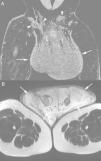

Post-contrast coronal computed tomography of the pelvis (A) showing isodense scrotal enlargement (arrows) with multiple fistulous tracts (arrowheads) in the right inguinal region. T2-weighted magnetic resonance image of the pelvis (B) showing hyperintense scrotal enlargement due to significant subcutaneous edema (arrows).

A 42-year-old black male, Brazilian farmworker presented with pain and progressive swelling of the scrotum for three years. He also had lower-limb edema, enlarged lymph nodes of the right groin, neck, and sternal furcula. A cervical lymph-node biopsy showed non-specific chronic inflammation. Serologies, including HIV, were negative. The nodule in the right groin increased in volume and gave rise to fistulization and purulent discharge. A chest X-ray was normal. Physical examination revealed a very enlarged scrotum with thickening of the skin and purulent discharge (Fig. 1). Computed tomography (Fig. 2A) and pelvic magnetic resonance imaging (Fig. 2B) showed a very enlarged scrotum with extensive subcutaneous thickening, and inguinal lymphadenopathy with multiple fistulous tracts in the skin. The left testicle had a reduced size, without testicular expansive lesions, and there was also bilateral hydrocele. Lymphoscintigraphy revealed an obstructive process in the inguinal region suggesting lymphatic involvement. The biopsy specimen of the right inguinal skin showed the “ship's wheel” appearance of yeast forms budding from the central parent yeast on silver stain, consistent with paracoccidioidomycosis (PCM) (Fig. 3). Serology for Paracoccidioides brasiliensis, based on double radial immunodiffusion test, was reagent (1:64). The patient was treated for 21 days with liposomal amphotericin B, followed by one-year treatment with oral trimethoprim/sulfamethoxazole (TMP/SMX). The patient remains on treatment. Later, a scrotoplasty was also performed.